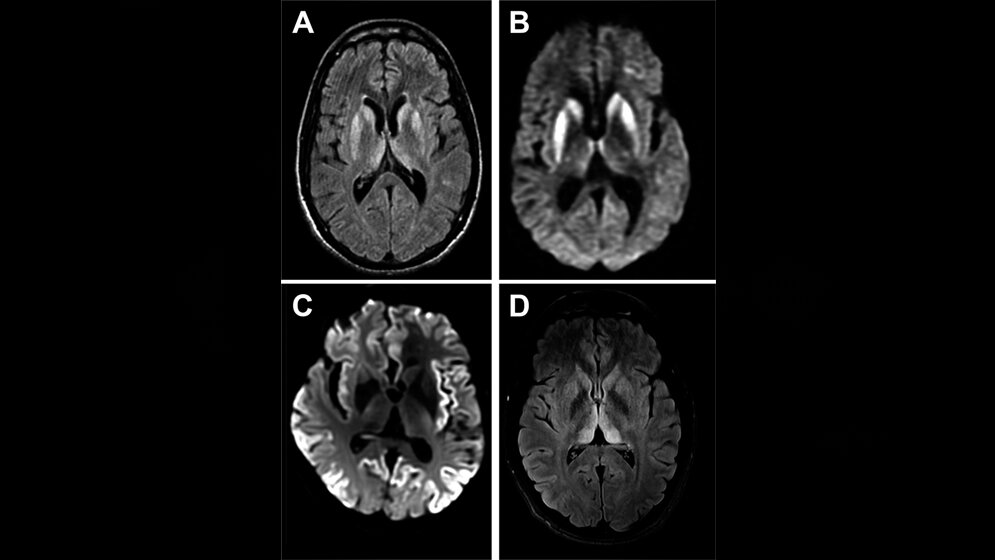

MRT der sporadischen CJK

MRT der sporadischen CJK* Pract Neurol, DOI: 10.1136/practneurol-2016-001571, open access, no changes, CC BY 4.0, https://creativecommons.org/licenses/by/4.0/

*(A und B) Sporadische CJK (FLAIR) (A), diffusionsgewichtete Sequenz (B), (C) diffusionsgewichtete Bildgebungssequenz bei sporadischer CJK, (D) Variante der CJK FLAIR-Sequenz